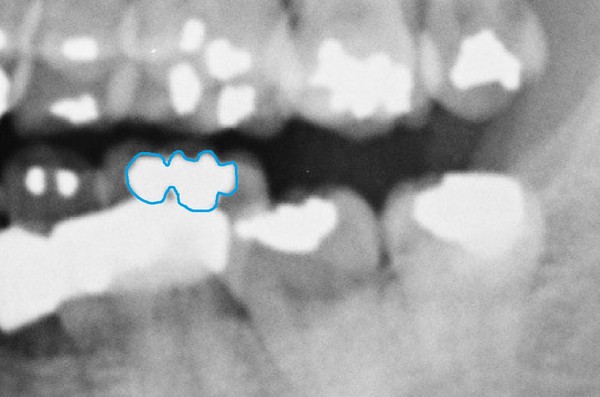

- ▲ 45번 치아를 촬영한 치근단 엑스레이(위)와 자생병원 구외 엑스레이(아래). 구외 엑스레이에서는 치수가 다소 비대한 경증의 우상치 형태를 띠고 있으나, 치근단 엑스레이는 정상적인 치아의 모습을 보인다. ⓒ 제공 치과의사 김우현

다섯 번째는 하악 구치부의 우상치(taurodontia)다. 우상치는 치수강이 치근단쪽으로 확장된 형태다. 먼저, 치근단 엑스레이에서는 우상치가 보이지 않는다.

그런데 구외 엑스레이는 36, 46, 47, 48번 치아 모두 경증의 우상치 형태를 보이고 있다.

<김>: 실제 박주신씨 인물사진은 웃고 있는 모습인데, 45번 치아가 보인다. 문00씨가 작성한 치료차트상으로는 주신씨 치아 45번 자리에 캔틸레버 브릿지를 한 것으로 돼 있고, 이는 자생병원 구외 엑스레이에도 나타난다.문씨는 2014년 6월 검찰 대질조사에서 주신씨에게 시술한 캔틸레버 브릿지에 대해 메탈 바깥에 포세린을 덧붙였다고 진술했다. 그런데 지난 9월 있었던 공판에서는 메탈로 했는지 포세린인지, 레진인지 기억이 안난다고 말을 바꿨다.

만일 문씨가 포세린을 사용했다면, 구외 엑스레이 상으로 확연히 나타나야 한다.

메탈은 X선이 투과하지 못하지만 포세린은 어느정도 투과하기 때문에 엑스레이상으로 부옇게 보이기 때문이다.

하지만 자생병원 구외 엑스레이에서 보이는 45번 치아는 부옇게 나타나지 않고, 전체 메탈부분이 명확하게 보인다.